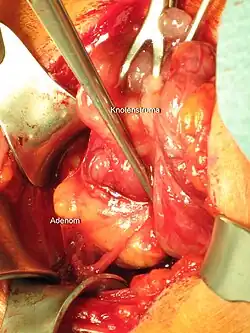

Liegt der vermehrten Bildung von Parathormon eine gutartige Geschwulst (Adenom) der Nebenschilddrüse zugrunde, spricht man von einer primären Überfunktion der Nebenschilddrüsen (primärer Hyperparathyreoidismus). Kennzeichen des primären Hyperparathyreoidismus sind ein erhöhter Parathormon-Spiegel und ein erhöhtes Serum-Calcium.

Die Therapie des primären Hyperparathyreoidismus erfolgt durch operative Entfernung des Nebenschilddrüsen-Adenoms. Ist eine Operation nicht möglich oder wird diese nicht gewünscht, kann bei geringgradig erhöhtem Serum-Calcium der Krankheitsverlauf durch regelmäßige Kontrollen von Parathormon und Calcium beobachtet werden. Bei stark erhöhtem Calcium kann die Bildung von Parathormon durch das Medikament Cinacalcet gehemmt werden.

- In 89 % der Fälle von primärem Hyperparathyreoidismus wird eine einzelne gutartige Geschwulst (Adenom) der Nebenschilddrüse gefunden, in etwa 5 % der Fälle finden sich zwei Adenome.[47] Die meisten Adenome werden von den Hauptzellen der Nebenschilddrüse gebildet und sind von einer Kapsel umgeben. Gelegentlich werden Adenome gefunden, die aus oxyphilen Zellen bestehen, diese Adenome sind in der Regel größer. Es gibt auch Parathormon-bildende Adenome im Thymus.[48]